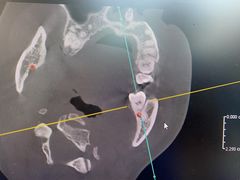

• 牙博士口腔品牌连锁(杨浦店)

• -牙博士口腔品牌连锁(杨浦店)

匿名用户 | 24-07-07